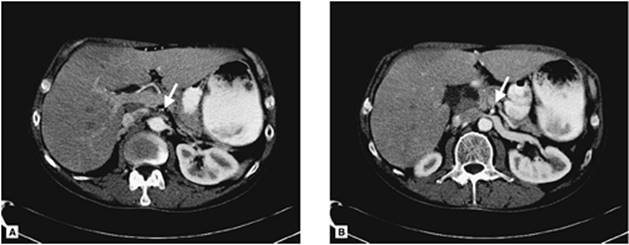

Patients with mesenteric venous thrombosis usually present with vague, mild abdominal pain. The pain is usually insidious in onset and frequently present for some time before the patients seek medical attention. Furthermore, the pain is not usually localized to any specific quadrant. Physical examination is notable only for mild, diffuse abdominal pain. Peritoneal signs suggest bowel infarction, but are found only later in the disease process. An abdominal CT scan is the diagnostic study of choice (87,88). The significant findings include bowel edema and thrombus within the mesenteric veins with inflammation of the vessel wall (Fig. 159.6). Plain abdominal radiographs may suggest abdominal wall edema and are helpful to rule out other causes of the abdominal pain. Standard catheter-based contrast arteriography may be helpful but is inferior to CT. The arteriographic findings that suggest mesenteric venous thrombosis include arterial spasm with a prolonged arterial phase, opacification of the bowel wall, extravasations of the contrast into the bowel lumen, and visualization of the venous thrombus.

Figure 159.6. A CT scan of a patient with mesenteric venous thrombosis is shown. Note the thrombus in the superior mesenteric vein at its confluence with the splenic vein as shown with the arrow.